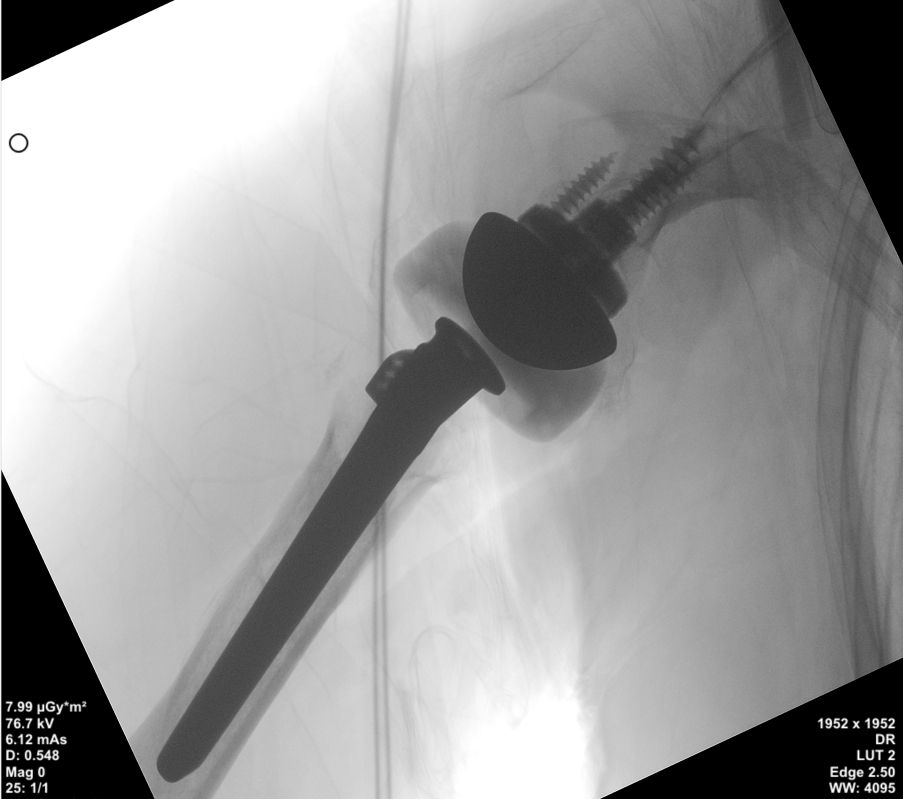

在导针的精准定位后,为患者置入肩盂侧假体组件,以及后续肱骨侧假体组件,顺利完成手术。手术共计耗时2小时,出血不到200ml,术后复查X片也显示假体植入位置非常满意。

肩盂侧假体组件及后续肱骨侧假体组件置入。